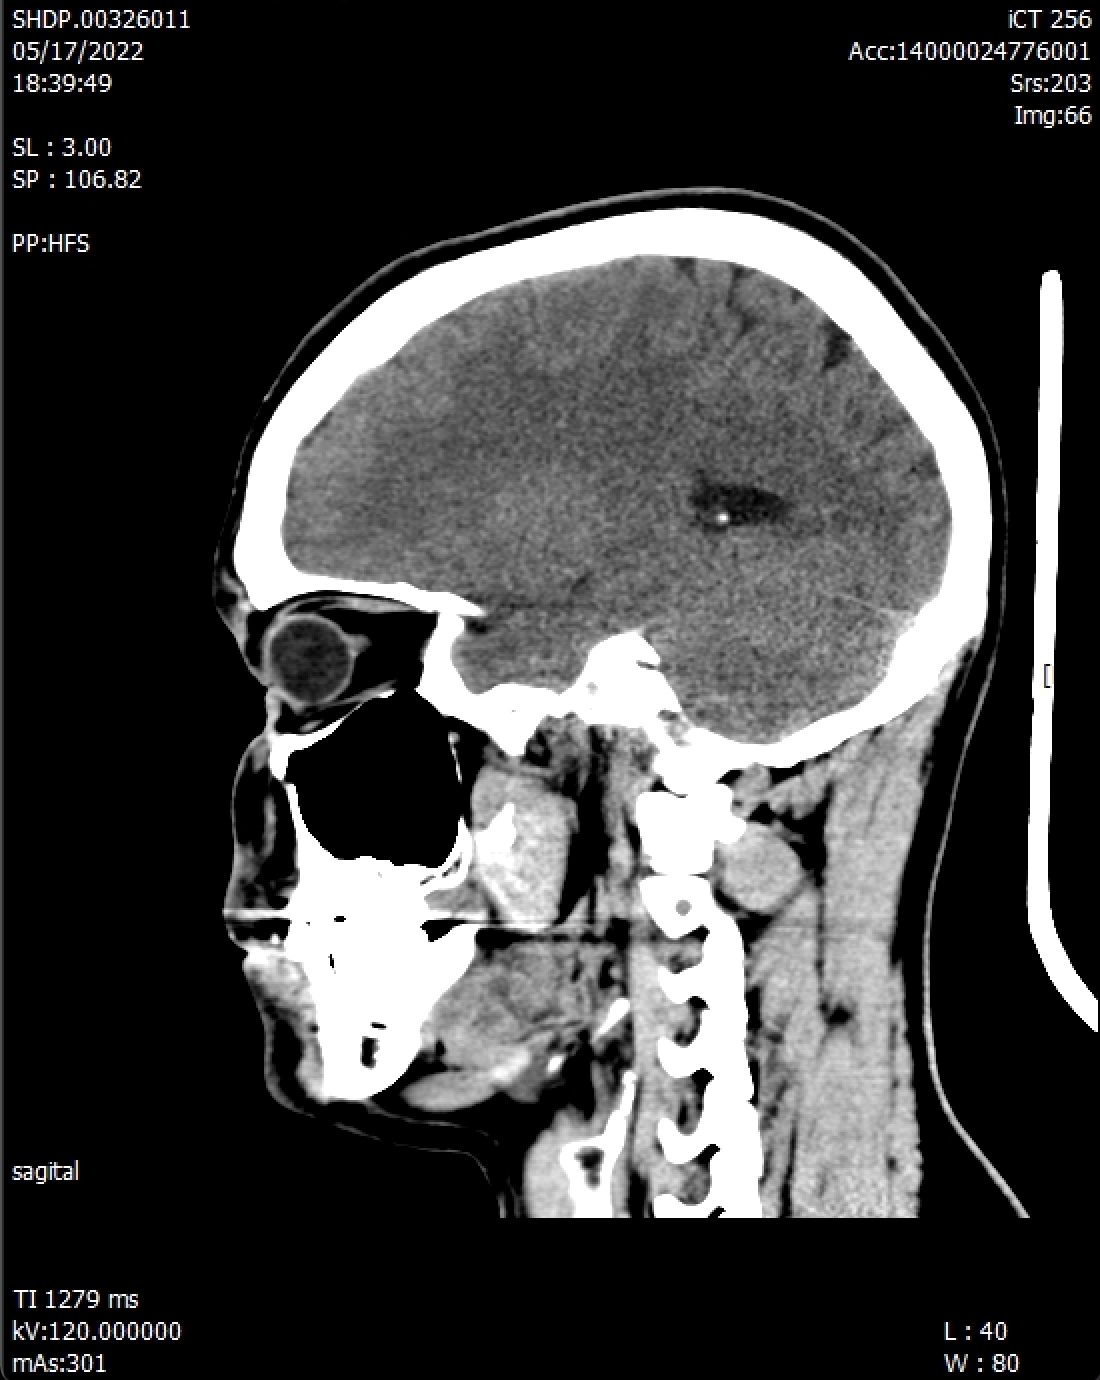

• Un petit traumatisme crânien

• Qui inclut visite médicale

• Scanner de la tête

Mais comment je suis arrivé à me faire un trauma au crâne ? (qui au passage est vide -> preuve plus bas)

Voilà, il a suffi de faire un peu le con dans l’eau pour se fracasser le crâne contre une paroi de celle-ci. Heureusement je n’ai pas perdu conscience sur le coup, sinon, je serais mouru.

Donc c’était consultation médicale, le lendemain bien sûr. Car bonhomme refuse d’admettre qu’il ne se sent pas bien.

Le médecin suspecte une éventuelle hémorragie donc il ne peut rien me prescrire pour ma tension élevée.

bonhomme n’admet pas que ça ne va pas, il attend le soir pour un scanner.

Le soir je décide de faire un scanner. Taxi —> Hôpital.

Scanner = -400€

Résultat disponible le lendemain. Car oui, malgré l’urgence, on ne peut pas donner de conclusions avant. Donc lessgo mourir à la maison.

On me dit que les résultats sont OK et RAS.

SVP les médecins qui lisent me dites pas que j’ai une tumeur surprise.